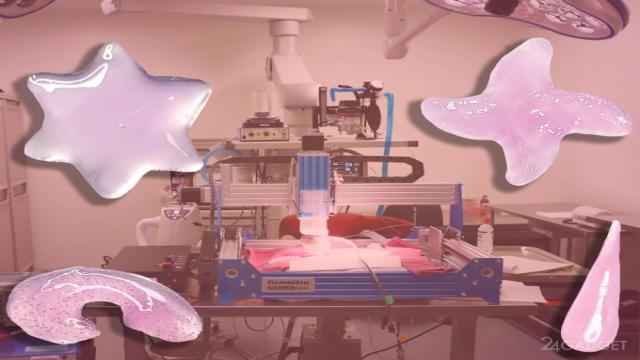

Сотрудники Калифорнийского технологического института представили систему Deep tissue In vivo Sound Printing (DISP). Технология позволяет печатать биологические ткани, датчики и лекарственные препараты прямо внутри организма без хирургического вмешательства.